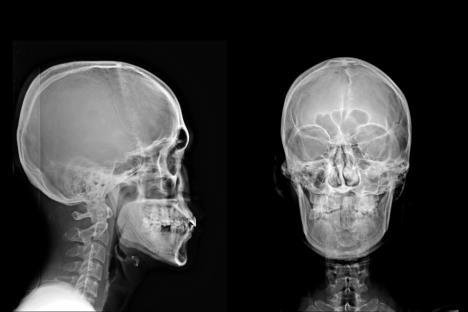

Bonus video: Kako se bebama snima grudni koš

Kako se bebama snima grudni koš Izvor: TikTok/overtime